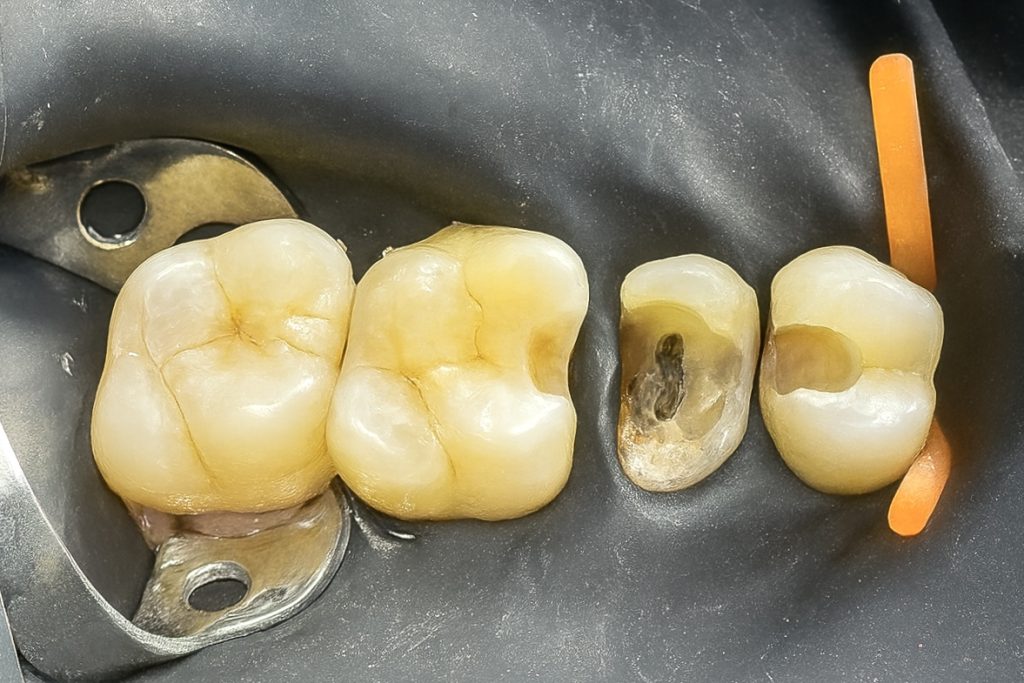

4️⃣ Molar Class II Preparation

Adjacent molar showed proximal caries extending sub-gingivally. Caries removal was done conservatively, followed by Deep Marginal Elevation (DME) using the Matrix-within-Matrix technique with flowable composite and a sectional matrix system (Fig 4).

- Fig 4: Molar Class II with Deep Marginal Elevation.

- Fig 5: Dentin replacement using GC EverX Flow.